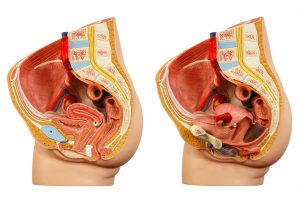

Pelvic organ prolapse risk raises with high body mass index (BMI) after pregnancy. Having a healthy BMI has been associated with overall good health, but having your BMI in the unhealthy range increases the risk of a number of various health issues, including heart problems – and organ prolapse. Maintaining a healthy BMI may also help prevent prolapsed pelvic organs, especially after pregnancy.

Pelvic organ prolapse risk raises with high body mass index (BMI) after pregnancy. Having a healthy BMI has been associated with overall good health, but having your BMI in the unhealthy range increases the risk of a number of various health issues, including heart problems – and organ prolapse. Maintaining a healthy BMI may also help prevent prolapsed pelvic organs, especially after pregnancy.

Nearly 50 percent of women over 40 who have given birth vaginally will experience pelvic organ prolapse, which can lead to bladder problems and poor bowel control.